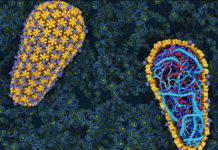

Anteriormente, los científicos en Alemania descubrieron que la transmisión del VIH está relacionada con la presencia de un amiloide fibrilar en el semen. Este fibrilar – una pequeña estructura, con carga positiva derivada de una proteína más grande – promueve la infección por VIH, ayudando a los virus encuentran y se unen a su objetivo: T CD4 células blancas de la sangre. En la edición de mañana de Cell Host & Microbe, los investigadores en el laboratorio de Warner C. Greene, MD, PhD, director de investigación de virología y la inmunología en Gladstone, describe un segundo tipo de fibrillas, que también tiene esta capacidad.

La transmisión sexual es para la inmensa mayoría de las infecciones por el VIH, y el semen es el modo de clave del virus de transporte. Estudios anteriores realizados por los Dres. Roan y Greene revela el mecanismo por el cual una carga positiva fibrilar en el semen – llamada SEVI – atrae el VIH como un imán, la unión a la carga negativa del VIH y ayudar a infectar a las células T CD4. En este caso, se dedicaron a investigar si los otros componentes del semen también jugó un papel.

En experimentos de laboratorio sobre muestras de semen humano, se identificó un segundo grupo de fibrillas -derivados de las grandes proteínas llamadas semenogelins – que mejoran la infección por el VIH así como SEVIhace. La eliminación de estos y otros componentes de carga positiva del semen disminuye la capacidad del VIHpara infectar las células T CD4 de sangre blancas. Lo que confirma el papel de estas fibrillas en la promoción dela infección por